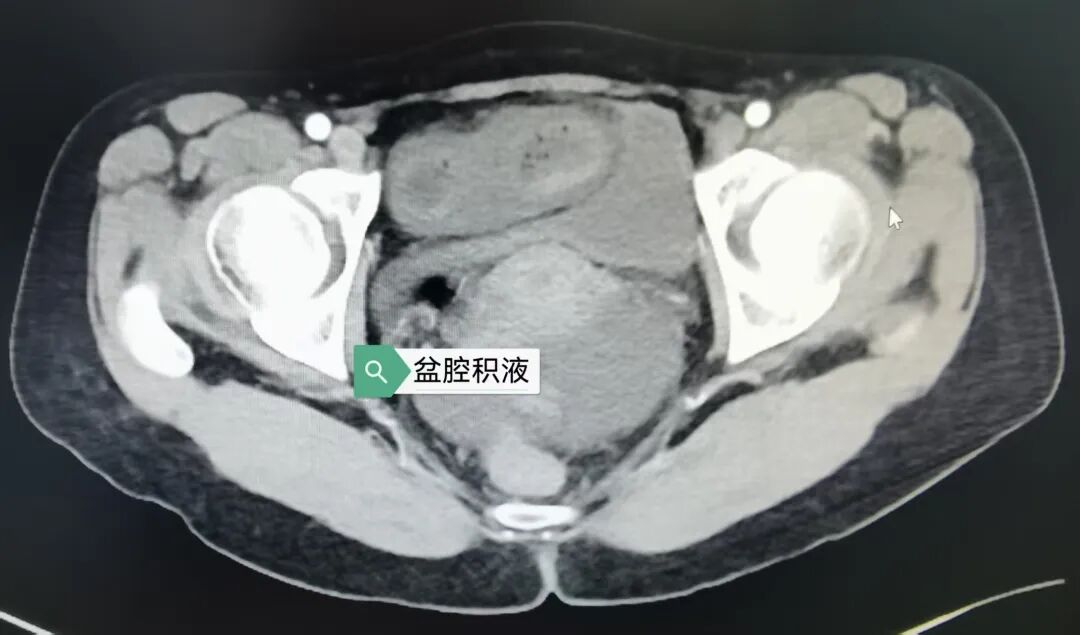

当天下午,被紧急转送至苏州京东方医院急诊科时,小李的脸色已经苍白如纸。急诊科医护人员立即启动绿色通道,腹部增强 CT 检查提示——盆腔右侧急性绞窄性肠梗阻,肠壁已出现缺血改变,盆腔内还有大量渗液。

急诊科、普外科、麻醉科、手术室……多个科室医护人员迅速联动,普外科朱玉喜主任医师、熊振医生从家里紧急赶来支援。办理入院、胃肠减压、静脉输液、术前检查,一切都在争分夺秒中有序进行。

原来,小李此前曾接受过剖腹产手术,术后形成的粘连索带就像一道「隐形枷锁」,缠绕住了她的小肠,导致肠管缺血坏死。这种情况如果延误治疗,可能造成感染性休克、脏器衰竭。